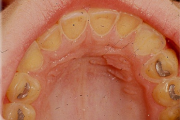

Vali sind huvitav pilt ja me näitame sellega seotud haigust ja sümptomeid